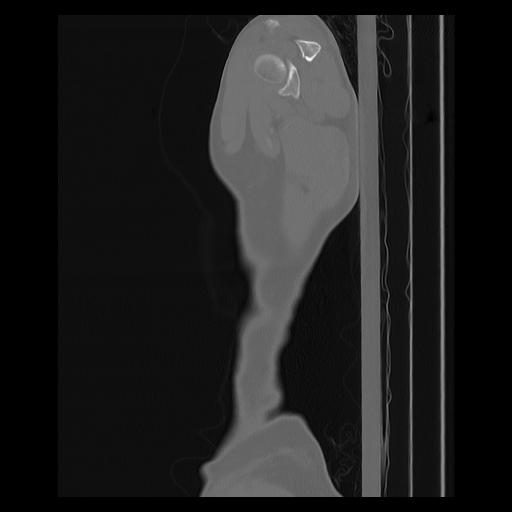

33 PULMON,CE,Sagittal,3.000,PULMON,Sagittal,